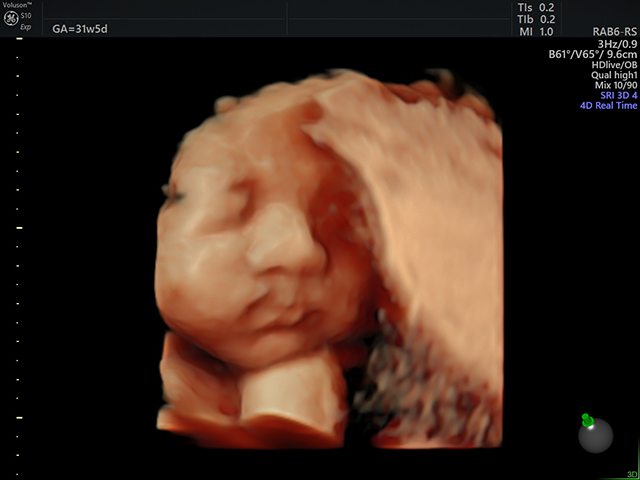

3D・4D超音波検査も実施しています。(撮影可)